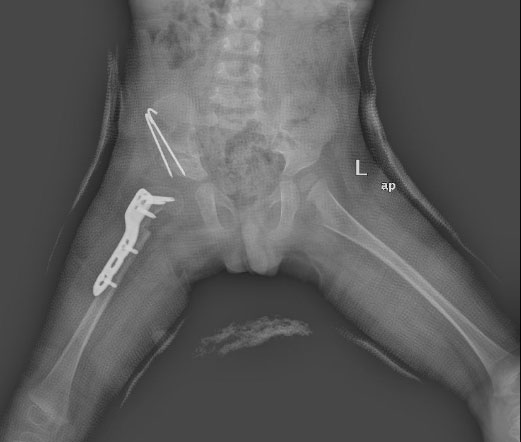

患者入院后,小兒骨科針對(duì)患者病情及時(shí)召開(kāi)病歷討論專題會(huì),經(jīng)分析該患兒由于髖關(guān)節(jié)發(fā)育不良、病變累及髖臼、股骨頭、關(guān)節(jié)囊、韌帶和附近的肌肉,出現(xiàn)髖關(guān)節(jié)脫位。患兒右股骨頭位于Perkins方格外上象限,Shenton氏線不連續(xù),雖然經(jīng)Pavlik挽具(吊帶)及(髖人字)石膏褲固定仍不能維持復(fù)位,手法復(fù)位治療無(wú)效。小兒骨科采用目前最有效、可靠的手術(shù)方式,選擇右側(cè)發(fā)育性髖關(guān)節(jié)脫位切開(kāi)復(fù)位,骨盆Salter截骨骨針固定、關(guān)節(jié)囊緊縮、髖臼成形,股骨轉(zhuǎn)子下截骨、短縮、角鋼板固定、內(nèi)翻去旋轉(zhuǎn),髖人字石膏固定術(shù)。手術(shù)歷經(jīng)3小時(shí),順利完成。

術(shù)后小兒骨科按照術(shù)前制定的護(hù)理及康復(fù)方案,指導(dǎo)患者進(jìn)行康復(fù),患者于近期治愈出院,經(jīng)隨訪復(fù)查,術(shù)后恢復(fù)良好。隨后,患患兒還需要經(jīng)歷術(shù)后截骨處愈合、股骨頭塑形、髖臼包容股骨頭等,逐漸恢復(fù)髖關(guān)節(jié)的解剖結(jié)構(gòu)并逐漸負(fù)重行走回歸生活。